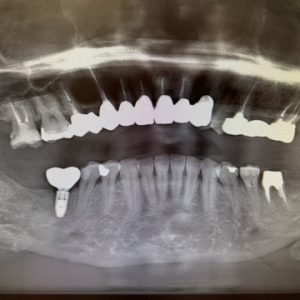

皆様こんにちは!歯周病専門医、かみ合わせ専門医の資格をもつ審美歯科医 石田智子です。セラミック治療についてはお気軽にご相談くださいませ。 最近、このようなパノラマレントゲンか...